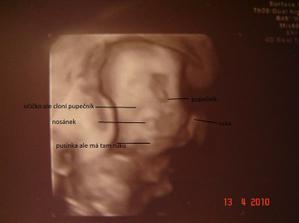

-28.4 kontrolní velký ultrazvuk Tak jsem doma s ultrazvuku a vše je v pořádku plodovky je normální množství a hematom tam není placentu mám prý na zadní straně vysoko tak ze začátku byla pořád na přední straně nizko naposled byla na zadni stěně nízko a ted už je vysoko tož jsem s toho jelen 🙂 hlavně že je vše v pořádku 🙂 a je to teda opravdu holčička nic se nezměnilo pindík nedorostl 🙂